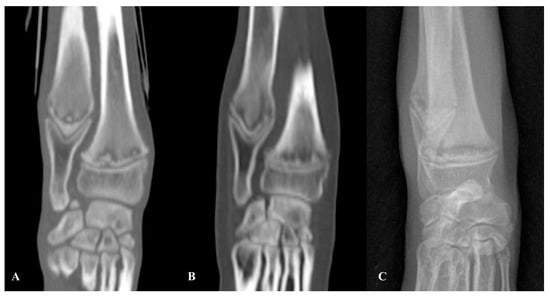

The included portions of appendicular skeleton showed bilateral, symmetric, irregular hypoattenuating metaphyseal bands of lysis bordered by sclerotic bone, located parallel to the physes of the proximal humerus, distal radius and ulna, distal femur, and proximal and distal tibia (Figure 4). These findings were suggestive of MO. Mild generalised superficial lymphadenomegaly was noted and was suggestive of a normal age-related finding or mild reactive hyperplasia. The remaining structures were normal.

Figure 4. Case 3. Sagittal (A) and dorsal (B) MPR CT images of the right stifle. Both the distal femoral and the proximal tibial metaphyses show an irregular thin hypoattenuating band (white arrows) with adjacent increased bone attenuation, consistent with osteosclerosis.